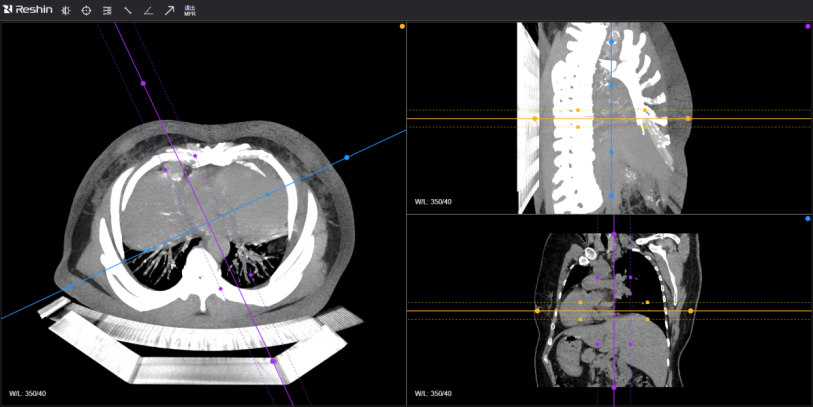

放射影像軟件——支持影像數據的接收、瀏覽;影像放射后處理及分析;三維后處理。

(影像放射后處理及分析)

(三維后處理)